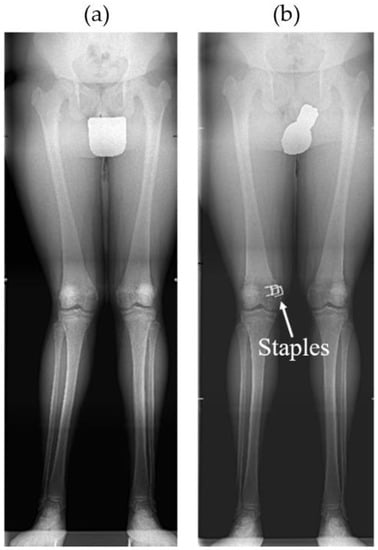

Using staples, the physis (epiphyseal plate) can be relatively simply restrained either on both sides when correcting limb length discrepancy (i.e., “epiphysiodesis”) or only on one side when correcting angular deformities (i.e., “hemiepiphyseodesis”) (see Figure 1 and Figure 2). Unlike the irreversible method of permanent epiphysiodesis, see [8], epiphyseal stapling does not destroy the epiphyseal plate and, therefore, allows resumption of the growth once the optimal correction is achieved; see [4].

According to [1,4], besides accurate diagnosis confirmed by a radiogram of the whole limb (see Figure 2), good timing of the treatment is also very important. The surgical procedure involves a short longitudinal incision through soft tissues over the physis and extraperiosteal implantation of the staple using a special instrument under radiography control [11] (see Figure 3). The staple must bridge the physis but not penetrate it to prevent its impairment (see Figure 4).

Figure 2. (a) Long radiogram of preoperative genu valgum and (b) consecutive correction with staples in femur; see [4].